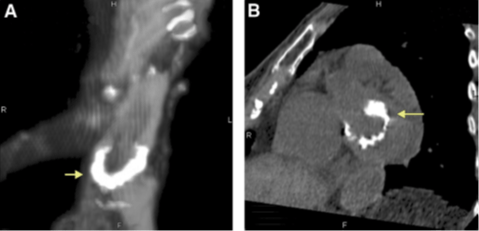

Grazie anche al suo lavoro sappiamo quindi che anche gli Egizi – o almeno le persone più abbienti – soffrivano di aterosclerosi. Se non ci stupisce che Ramses II alla sua veneranda età avesse le arterie con significative calcificazioni e che suo figlio Merenptah avesse un’aorta che era ormai rigida come il legno, ci potrà sorprendere che Lady Teye, una donna vissuta all’epoca della XXI Dinastia e morta all’età di 50 anni, ritrovata a Deir-el Bahari, avesse la valvola mitralica già calcificata, le coronarie occluse e l’aorta con ateromi nodulari.

Sezione dell’aorta di Merenptah, con le lamelle muscolari dell’intima media inframezzate da depositi di fosfato di calcio, nel disegno originale di Shattock del 1909 (A Report upon the Pathological Condition of the Aorta of King Menephtah, traditionally regarded as the Pharaoh of the Exodus. Proc R Soc Med. 1909;2(Pathol Sect):122-7